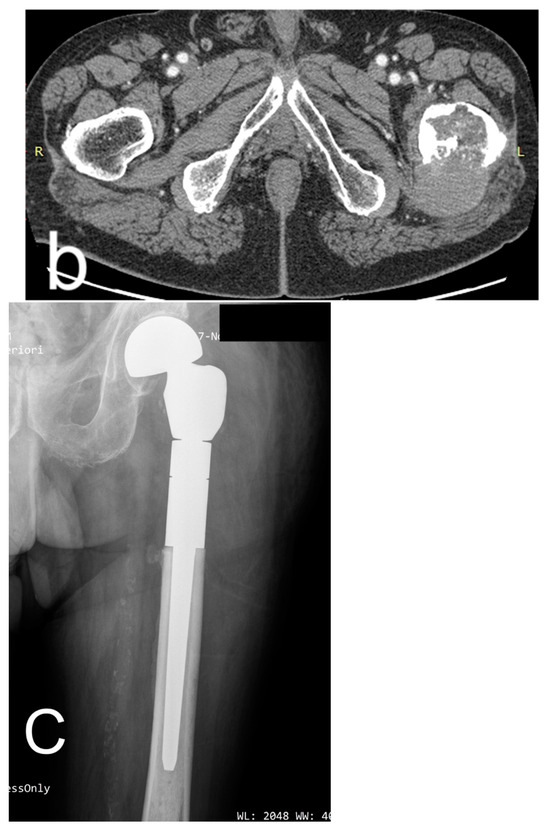

Characteristics of oncological patients are shown in Table 1. Among 15 procedures in tumor patients, one-third was performed for primary bone or soft tissue tumors, with chondrosarcoma representing the most frequent histotype, accounting for 80% of primary tumors and 100% of primary bone tumors (Figure 1).

Figure 1.

(a) Male, 84 years old, affected by dedifferentiated chondrosarcoma of the left proximal femur; CT coronal reconstruction of the proximal femur. (b) Axial CT scan shows extraosseous extension of the tumor. (c) Resection and reconstruction with a cemented proximal femur megaprosthesis were performed. The patient lived for 10 years (122 months) after surgery with no tumor recurrence and was able to walk with the aid of a cane. He died at 122 months due to a concomitant disease.